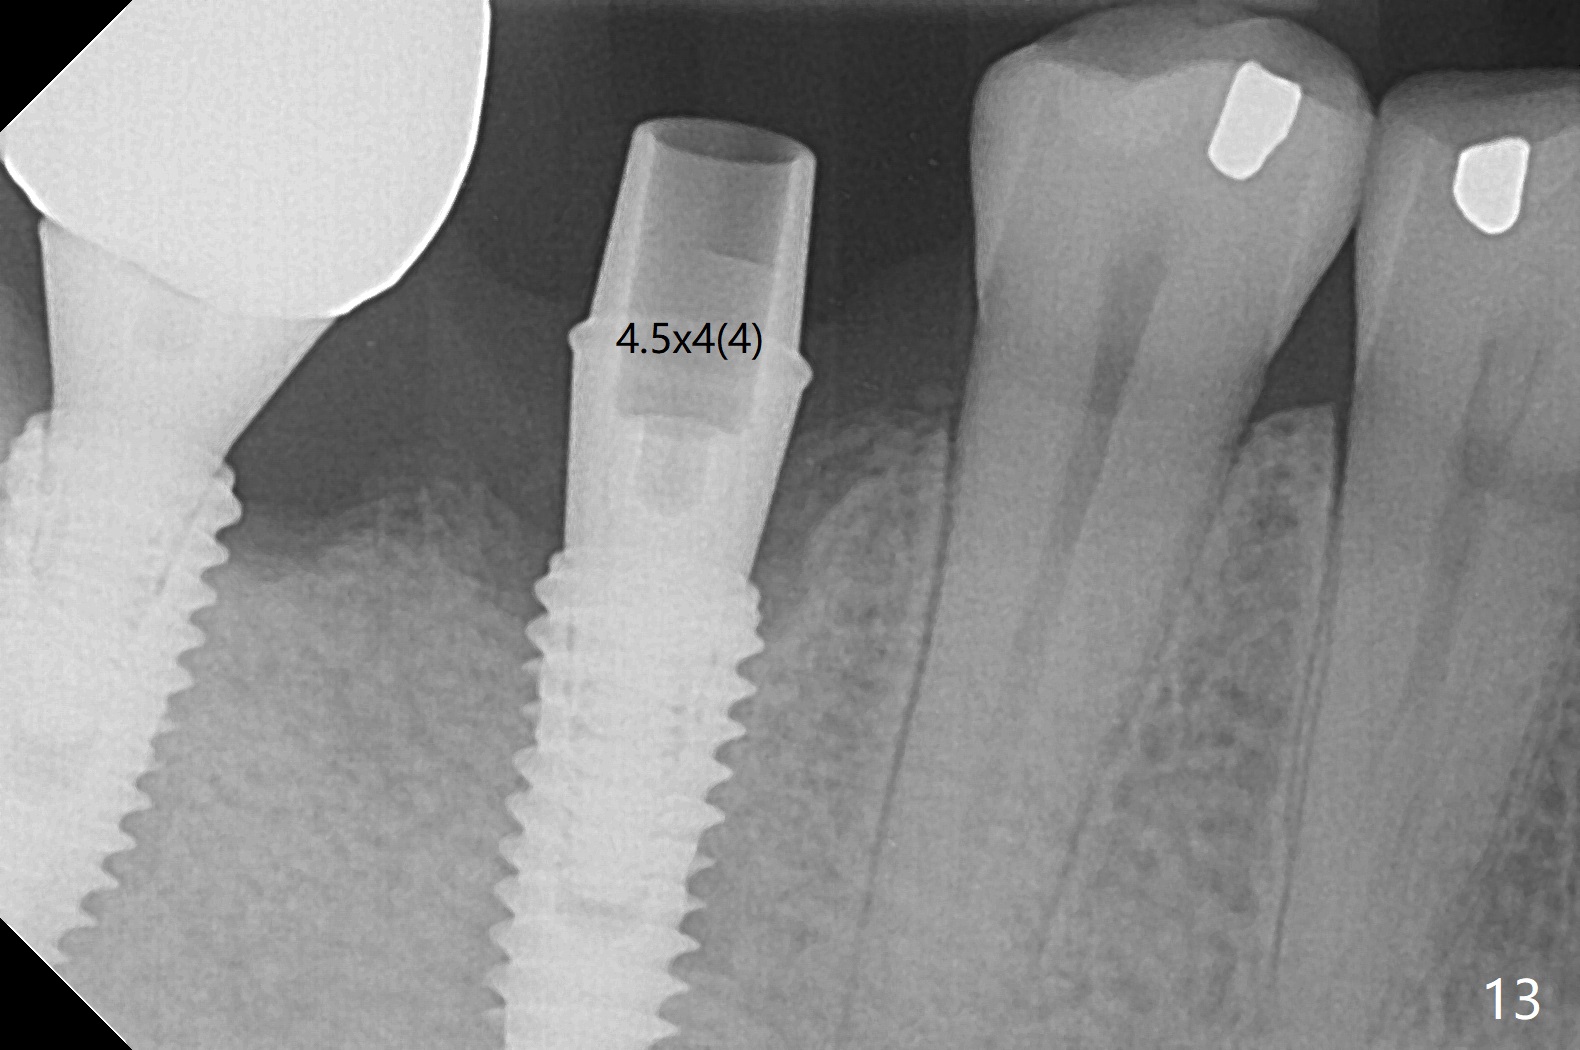

Infection is not so typical.  There is no recent postop X-ray, just 18-19 days postop.   Thanks for the reply.  We will keep watching.  The healing abutments, loose and associated with gingival inflammation, are removed 2.5 months postop (Fig.4).  There is crestal bone resorption, although the implants are stable.  The crestal bone resorption persists especially #30 distal 4 months postop (Fig.5 *).  When the implants are uncovered, there is mild bone loss distobuccal to #30 implant, consistent with early periimplantitis.  Bone graft is placed after debridement and healing abutment placement.  There appears no bone loss nearly 9 months postop (Fig.6).  The soft tissue looks healthy.  Cementation abutments (5.7x4(3) and 5.7x4.5(3) mm at #30,31, respectively) are placed for impression.  The distobuccal gingiva at #30 is hyerplastic 10 months postop (Fig.7 *, immediately before cementation), which is consistent with bone loss (Fig.8,9 * (periimplantitis)).  It is hoped that the infection will dissolve with improved oral hygiene (water pik) over the smooth final restoration.  In fact it is, i.e., the implants at #30 and 31 remain asymptomatic with the healthy gingiva 6 months post cementation (Fig.10,11).  There is mild crestal bone loss at #30 and 31 ten months post cementation (Fig.12).  Crown/implant ratio is the basis for screw loosening.  In fact the crown/abutment at #30 is loose 4 months later.  Incomplete seating of the abutment may be a culprit (Fig.12).  The gingival cuff is not healthy; a 6.8x7 mm healing abutment is placed with gingival blanching with Cetacaine and antibiotic ointment.  Next visit place a new smaller diameter abutment (4.5 or 5.2) with probably longer cuff (4 mm) or the existing abutment with no proximal contact crown, torque 25-30 Ncm and take BW with sensor 2 or PA with sensor 1.  In fact there is resistance to hand tighten a 4.5x4(4) mm healing abutment, which is due to contact with the mesial crest (Fig.13 *).  After use of 5.5 and 6.0 mm profile drills, the 6.8x7 mm healing abutment is reseated.  The latter appears to contact the mesial crest (Fig.14).  Later a 6x5 mm healing abutment is placed.  New crowns with new abutments are delivered 2 years 3 months postop (post Coronavirus lockdown).